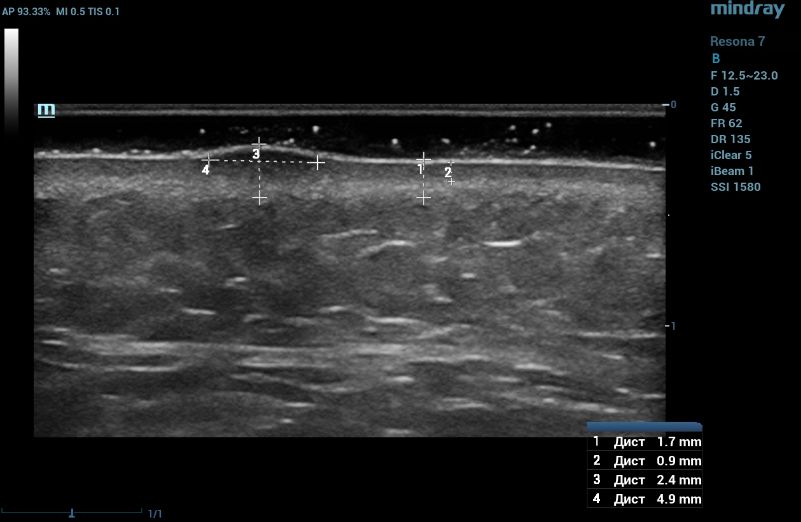

Ultrasound examination of the nevus was performed on the Resona 7 ultrasound machine (Mindray, China) using the high frequency linear transducer L20-5U (max frequency 23 MHz). When the transducer was placed in the projection of the visible nevus of the right zygomatic region of the face, the derma was locally thickened to 2.4 mm due to a hypoechogenic mass located under the epidermis and slightly elevated, spreading in depth to all layers of the dermis with clear rough boundary of heterogeneous echogenicity, without hyperechogenic sports, giving a weak acoustic darkening of the echo signal (Figure 2). Blood flow is not registered inside the nevus in the Color Doppler mode (Figure 3).

Ultrasound examination of the nevus in B mode

Figure 2. Ultrasound examination of the nevus in B mode

Such ultrasound signs are characteristic of compound nevus [2]. A pronounced subcutaneous low-echo band (SLEB) attracts attention (0.9 mm – 50% of the total thickness of the dermis – 1.7 mm), which is the ultrasound sign of facial skin photodamage [3].